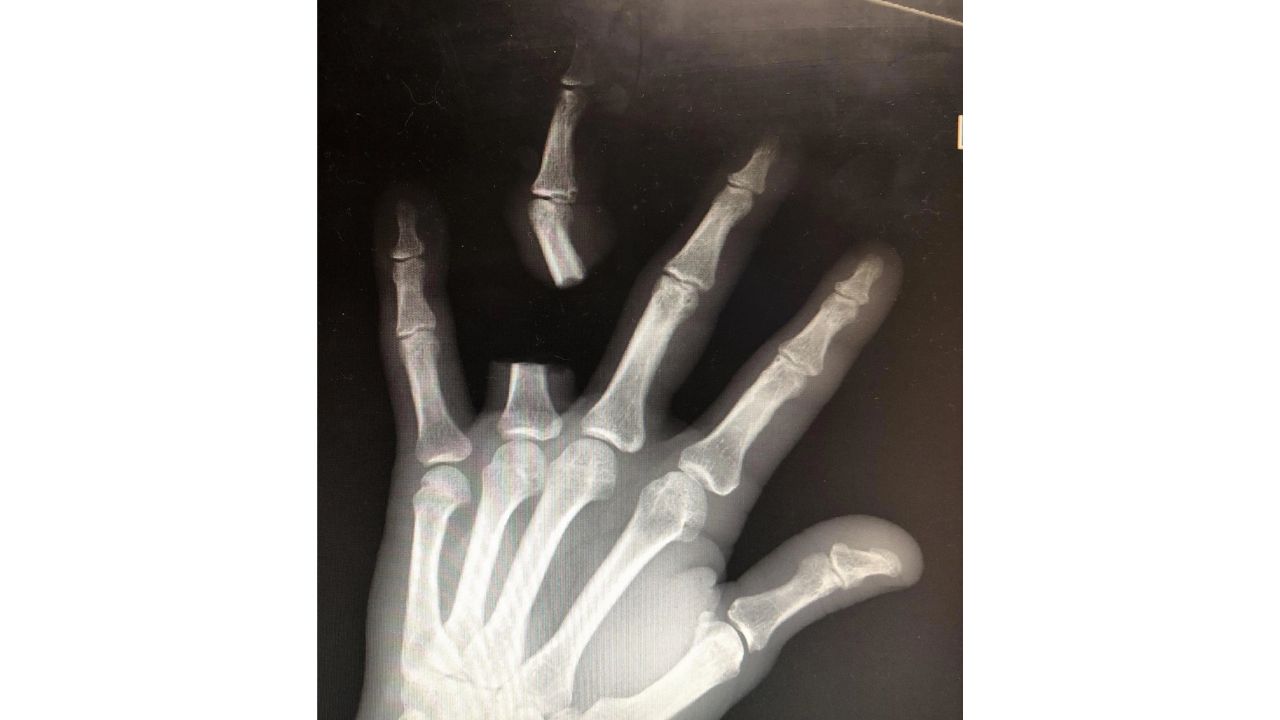

Após cortar o dedo, Zhang percorreu aproximadamente 80 quilômetros até um hospital, buscando atendimento emergencial. No entanto, ao chegar à unidade de saúde, foi informado pelos médicos que o réptil não possuía veneno letal. De acordo com os profissionais, o animal tratado como ameaça era, na verdade, uma espécie local não considerada perigosa.

Os médicos ainda relataram que não puderam reimplantar o dedo porque o idoso deixou o membro no local da ocorrência. Zhang passa bem, mas o caso ganhou repercussão na mídia chinesa e nas redes sociais como um alerta sobre decisões impulsivas em situações de emergência envolvendo animais peçonhentos.